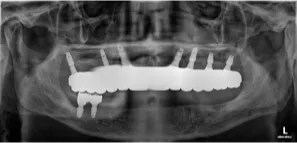

73세 고령의 남성환자분

지대치들이 파절되고 발치되어 내원하셨고 보철물 때문에 일상생활에 불편을 겪으셨습니다.

임플란트에 의한 재건을 원하셨으나, 골흡수가 심하고 하악구치부는 식립이 불가능하였습니다.

3D 모의시술로 발치 후 바로 임플란트 식립하고 임시 보철물 당일 장착하였습니다

초진 X-RAY (2023.10.05)

당일 임시 보철물 장착 (2023.10.23)

풀아치 임플란트 수술후 (2024.02.29)

최종 보철물 연결 (2024.02.29)